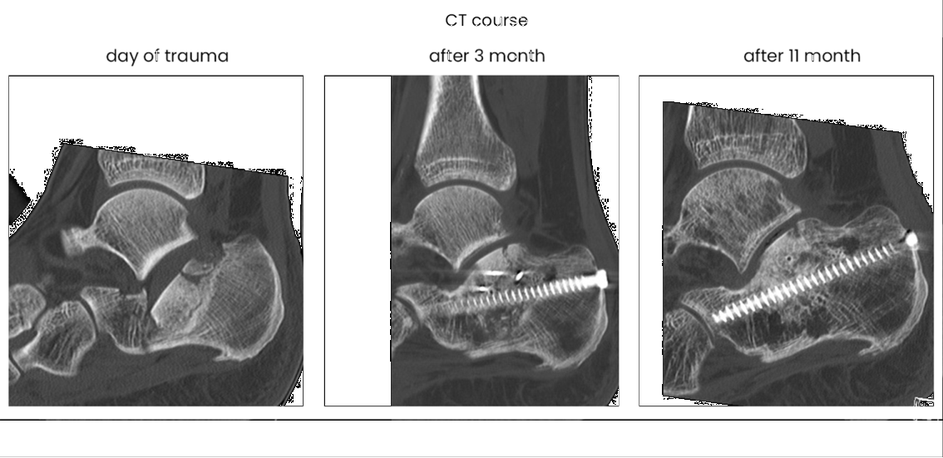

case 17BD, 47 years old, male, fall during work, 2 meters, "comminuted fracture", surgery after 2 days